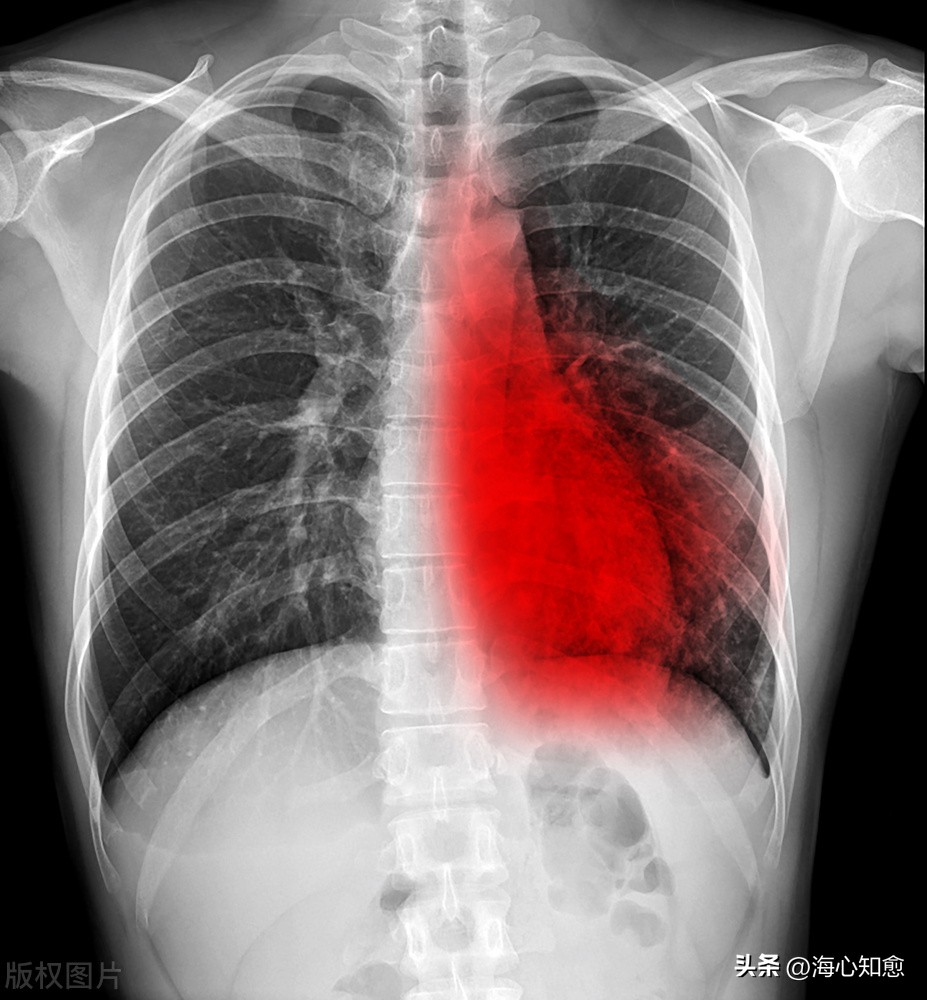

食管癌肺转移一般在随访原发肿瘤的过程中,进行胸部影像检查时被发现。

一般来说,当胸部CT 显示肺部出现弥漫性病变,或单发、多发的小结节,或类圆形、边缘规整块影,均要警惕转移的可能性。

尤其无钙化的多发结节,90%以上为转移瘤,而单发结节,诊断较为困难,仅2%~5%为转移瘤。

因此建议对食管癌患者随访时做胸部影像学检查,且在术后2年应在较短时间内进行复查,以尽可能及早发现复发和肺转移,从而调整治疗方案。